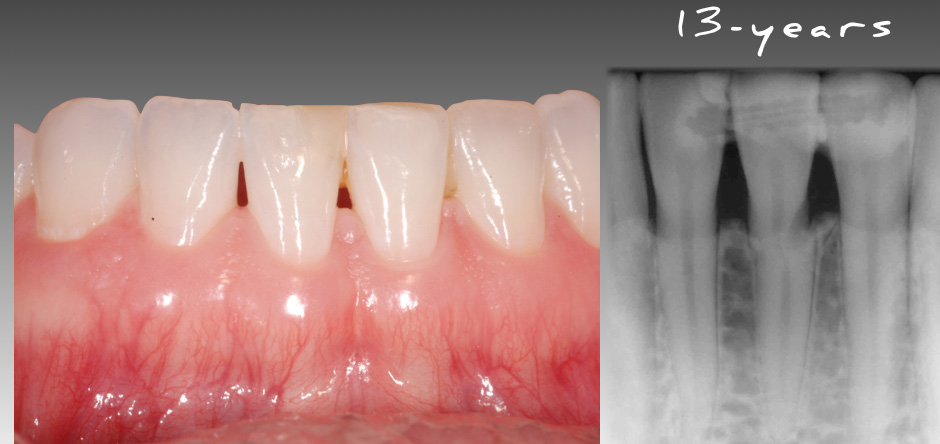

Looking at the image below, we can see that the fractured central incisor is still functional and serviceable at 13 years old. Although this case is not the norm (because of the long-term success despite the location of the fracture being in the cervical third), hopefully it makes you stop and think differently about managing teeth with horizontal root fractures.